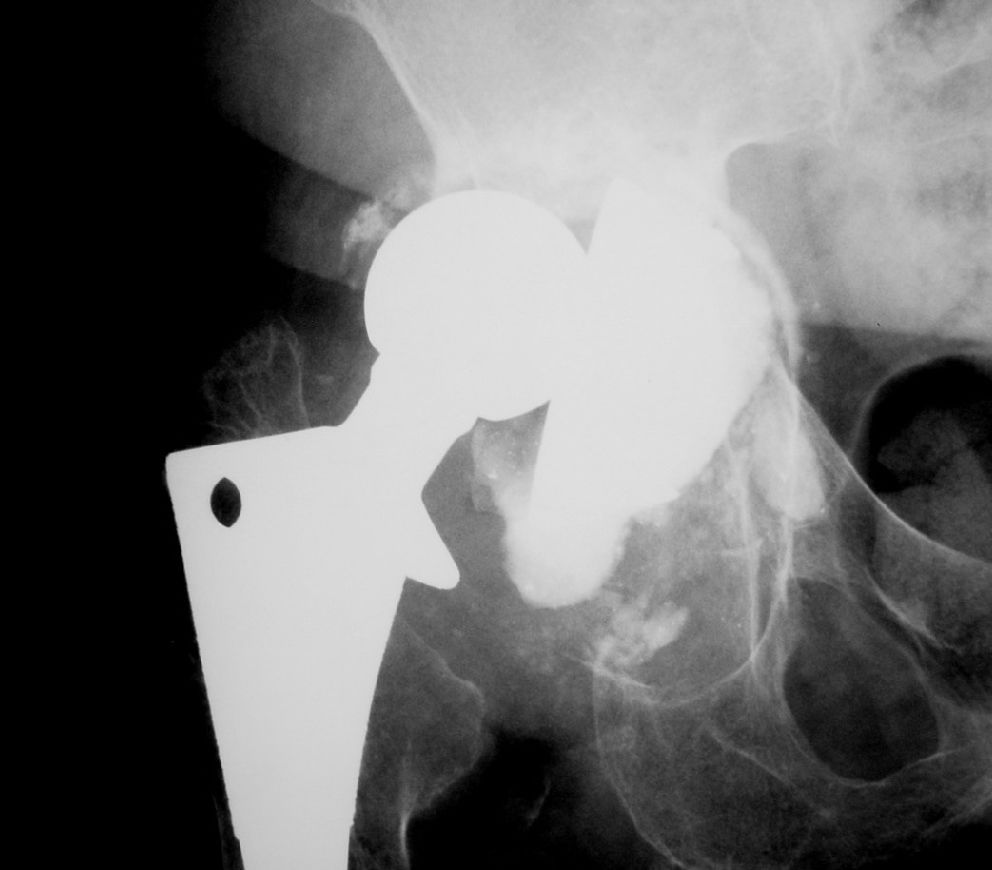

Overall, no minor events were observed clinically. However, in Group 1 a case of traumatic displacement three years after RTHA required surgical intervention, since attempts for clinical reduction failed. In this case, a histological analysis of the grafted region indicated there was an area of new bone formation and residual spicules from the graft material (Figure 1). In Group 2, a case of superficial infection (cellulitis) occurred six months after the procedure and was successfully treated with antibiotics. The clinical and radiographic outcomes are shown in Tables 2 and 3, respectively.